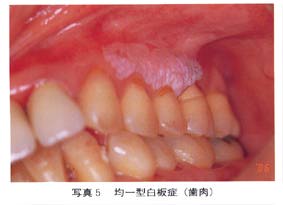

2.白板症 舌、頬粘膜、歯肉にできる白斑。 非喫煙者の6倍。17%が口腔癌になるとされます。 |